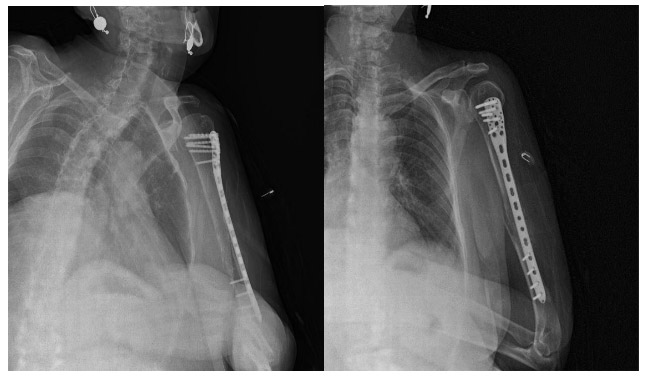

CASE 5: Fracture due to breast cancer metastasis to the left arm (humerus) bone.

Post-surgery: The image shows the application of fixation with an anatomical titanium plate.